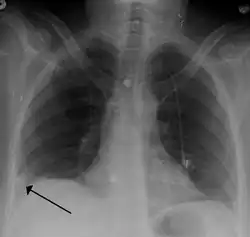

- Chest X-rays are often done on people with shortness of breath to help rule out other causes, such as congestive heart failure and rib fracture. Chest X-rays in PE are rarely normal,[70] but usually lack signs that suggest the diagnosis of PE (for example, Westermark sign, Hampton's hump).